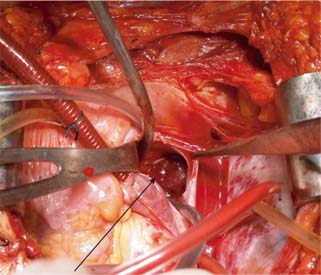

The surgical technique used for different levels of thrombus extension in our study is as follows. For level I (Figure 1) thrombus, vascular side clamps are used without occluding IVC inflow. The cavotomy defect is then sewn using a continuous prolene 4-0 suture. Level II thrombus (Figure 2A and B) often necessitates more extensive mobilization of the IVC. Proximal and distal control of IVC is necessary with ligation and division of lumbar veins to prevent significant blood loss. For the retrieval of thrombus, vascular clamps are used with clamping of the left renal vein in case of right-sided renal tumors and clamping of the right renal artery in case of left-sided renal tumors. The cavotomy defect is sewn using continuous prolene 4-0 suture. For level IV thrombi (Figure 3), a beating heart surgery with a simplified CPB technique was used for retrieval of thrombus from RA. For level IV thrombi, ligation of renal artery is followed by radical nephrectomy using chevron incision. The left renal vein is looped, and IVC below the renal vein is skeletonized for a length of about 5 cm to prepare it for IVC cannulation. A purse string is made on it using 4-0 prolene monofilament suture and the subhepatic portion of IVC is dissected. Then, median sternotomy is performed and pericardium is opened. Aortic purse-string suture with 3-0 prolene is taken on the ascending aorta. The intrapericardial portion of the superior vena cava (SVC) is looped, and a purse-string with 3-0 prolene is taken. Patient is heparinized with 300 Units/kg body weight of heparin. Aortic and venous cannulations are performed, and patient is put on complete CPB after both SVC and IVC are snugged with Rummel tourniquet. No vent cannula is put in. Patient is cooled to 35°C. On beating heart under normothermic CPB, RA thrombus (Figure 4) is extracted without cross-clamping the aorta. Right atriotomy is performed and tumor thrombus, which is organized and firm, is carefully retrieved. IVC is snugged at its junction with RA to prevent spillover from IVC into RA. Subhepatic IVC is incised longitudinally, and the tumor thrombus is extracted, using digital manipulation to ensure complete removal from retrohepatic IVC. Intermittent suctioning is performed using a pump sucker as hepatic veins are opened up. Cavotomy is closed using 4-0 prolene suture. After completely de-airing the RA, the atriotomy is also closed. Patient is gradually weaned off the bypass. “Patients were followed up quarterly in the first year, semiannually in the second year, and annually thereafter”.

Figure 4: Opening of right atrium with arrow showing thrombus in situ.

Approximately, 2–16% of RCC patients had extension of tumor thrombus to RA (46). In the 2010 International Union against Cancer TNM staging system, the diameter of renal tumors and the level of tumor thrombus are important prognostic indicators. This surgical procedure has two components for the excision of renal mass and IVC tumor thrombus. In our series, majority of patients had level I thrombus (55.88%), and histopathological examination of resected specimens (19 nos.) revealed squamous cell carcinoma in 03 cases (15.78%), clear-cell carcinoma in ten cases (52.63%), papillary carcinoma in 04 cases (21.05%), and chromophobe cell carcinoma in 02 case (10.52%). In this cohort of level I thrombus, 16 patients were alive till last follow-up until 5 years with no recurrence of tumor thrombus or distant metastasis. Three patients with histopathological examination HPE of squamous cell carcinoma died within 2 years of surgery and one patient developed lung metastasis. Of the 12 patients (35.29%) with level II thrombus, 10 (83.34%) had clear-cell carcinoma and two (16.66%) had papillary carcinoma. In the level IV thrombus group (8.8%), histopathological examination revealed clear cell carcinoma with sarcomatoid variant in all three cases and only two were completely resected. In one case only biopsy was taken in view of intraoperative hemodynamic instability. All the resected specimens had a negative margin. One patient with left RCC developed solitary lung metastasis during-follow up and was put on tyrosine kinase inhibitors (TKIs) by the medical oncologist. The patient behaved well but was lost to follow-up after 3 years. The more the length of the tumor thrombus, the more challenging it is, necessitating a multidisciplinary approach that increases the complexity of the management. “Radical resection is the only curative option for RCC with a tumor thrombus in the inferior vena cava, and accurate pre operative imaging is crucial for a positive surgical outcome”. Most patients with IVC extension can be treated with nephrectomy with IVC thrombectomy without putting the patient on CPB; however, in cases of RA extension (level IV), CPB is strongly recommended (5). Digital manipulation of tumor thrombus to push it from RA into IVC without CPB can cause life-threatening blood loss. CPB offers a bloodless field and hemodynamic stability during thrombectomy from IVC and RA (2, 79). There are, however, inherent complications associated with CPB, including increase in operative time, myocardial ischemia during cross-clamp, arrhythmias, respiratory complications, and postoperative hemorrhagic drainage due to onset of coagulopathies (5, 10). In literature, some surgeons have used profound hypothermia with circulatory arrest to retrieve the tumor thrombus from RA (11, 12). The predominant limitations of this technique are its associated morbidities, including neurologic complications (delirium, psychosis, and stroke) (13, 14), thrombocytopenia, and platelet dysfunction, resulting in significant bleeding, prolonged and/or improper rewarming with postoperative hypothermia, and overall higher mortality (13, 15). Our approach in level IV thrombus (Figure 5) was beating heart on simplified CPB without cross-clamp on aorta. Beating heart is more physiological, as the heart is allowed to beat normally, maintaining a normal coronary perfusion and contractility, while offloading the heart of blood volume. As a result, this allows for smooth resumption of heart off bypass. Weaning off from CPB is quick, smooth, and easy, without having to wait for the mandatory period to replenish the myocardium with energy substrates needed in the case of an arrested heart. This reduces the operative time, and facilitates better hemodynamic stability, early extubation, and early shifting from intensive care unit to the general ward. As a result of shorter CPB time, the inherent risks of extracorporeal circulation are minimized, although not eliminated. These include less systemic inflammatory response, less coagulopathy and thrombocytopenia, thereby less postoperative bleeding and blood transfusions; less chances of embolism, stroke, and post-CPB psychosis.